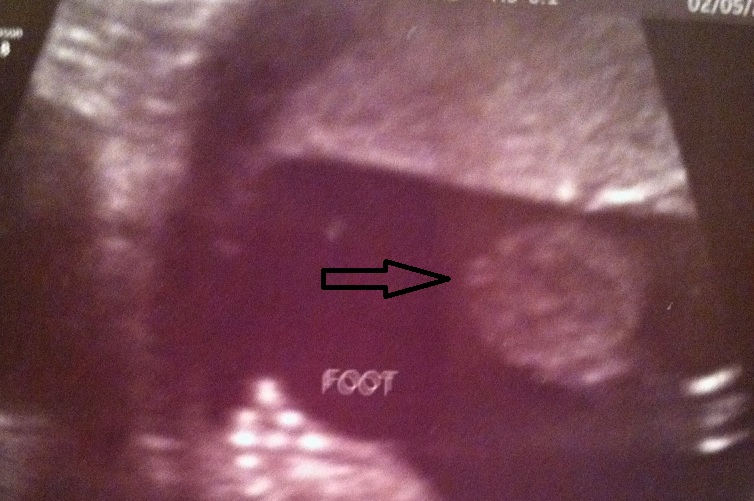

photo one is gender and foot. arrow pointing to gender, potty shot angle. pic 2 is just a baby shot. this is baby number 4. i have 2 living sons, and an angel boy. im hoping this is my girl! thats what ive been told thus far